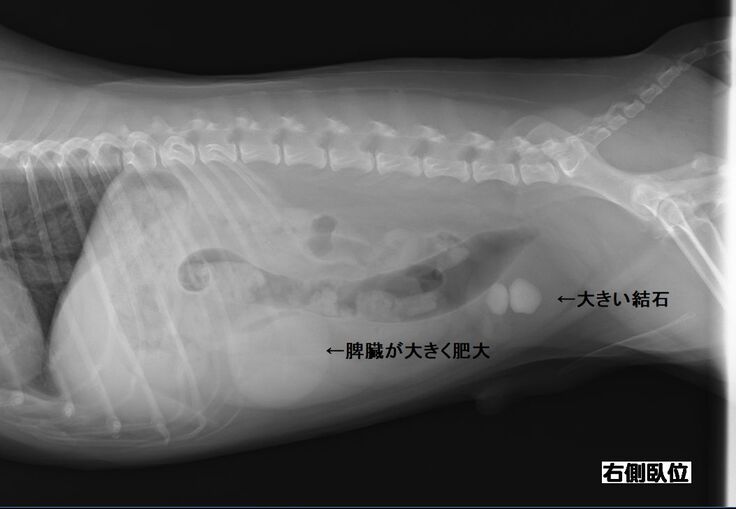

以前より下部尿路疾患で尿路結石を持っているチョコですが、膀胱にある結石が大きくなり膀胱を痛めて膀胱炎を頻繁に発症するようになりました。

膀胱炎から炎症が全身に、更には脾臓の腫瘍が確認されました。

検査の結果、脾臓肥大が限界近くの爆発寸前になっていることが判明しました。

脾臓は4センチまでなってるから、いつ破裂してもおかしくない状況。

現在9歳のチョコですが、脾臓はいずれ摘出した方が良いと獣医師より指摘されております。まだ若いので悪性の可能性は低いと言われています。また、結石も同時に摘出をした方が良いと。